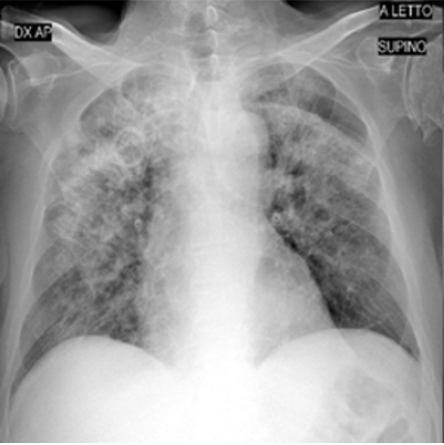

4.1 Qualitative Evaluation of Healthy Counterpart Generation

Example images from the disease COVID-19 Radiography Database and their generative healthy counterparts are given in figure 2. The images on the far left are instances of the lung opacity class from the real images in the dataset. The images in the middle column are examples of the generated healthy counterfactuals obtained via latent space diffusion, with RadBERT-guided textual-conditioning via a conditional prompt “normal chest x-ray”. A total of 75 diffusion inference steps are used with image conditioning strength=0.85 and guidance scale=7.5. (The former indicates the level of constraint on changes to the original input image and the latter is the weight given to the textual encoder conditioning in the generation of the image, ranging over [0,1] and [0,9], respectively).

Side-by-side inspection of the generated healthy counterfactuals (as per fig. 2) suggests that, as required, only minimal perturbation is made to the original image with respect to healthy pixels -i.e. localized image sites without structural medical defects. (In the top row, the medical structural defect in the original image is due to a lung opacity, and characterized via a relatively complex interaction between the imaging modality and subject manifesting as ‘gaps’ in the corresponding portions of the lung scan). The healthy/non-healthy discrepancy maps in all of these cases are obtained via masked subtraction of the original image from the generated image (the ground truth segmentation masks correspond to the broad area of interest –i.e. the complete lung). The generated healthy tissue is thus a subset of the mask and is shown in the final column of fig. 2 for the respective cases.

In the context of a VANT-GAN[20]-based approach, this highlighted material constitutes the diagnostic counterfactual visual attribution, i.e. the selection of material relevant to the diagnosis of the unhealthy condition. Healthy counterfactual generation was performed for the complete datasets in the three unhealthy classes, i.e Lung opacity, Viral Pneumonia and COVID, examples of which are given in fig. 3 for the three classes (all of the generated healthy counterfactuals from this experiment can be found on https://huggingface.co/ammaradeel/diffusionVA). Visual inspection indicates that the generated counterfactuals are, in general, visually plausible with minimal perturbation made to the unhealthy image overall. Moreover, the healthy counterpart generation does not appear to unnecessarily affect aspects of the images unrelated to the medical condition, the model selectively making changes to the unhealthy regions in a structurally plausible manner, e.g. generating missing portions of the lung without generating extraneous lung material where it would be expected to normally exist (e.g. in the abdominal cavity).